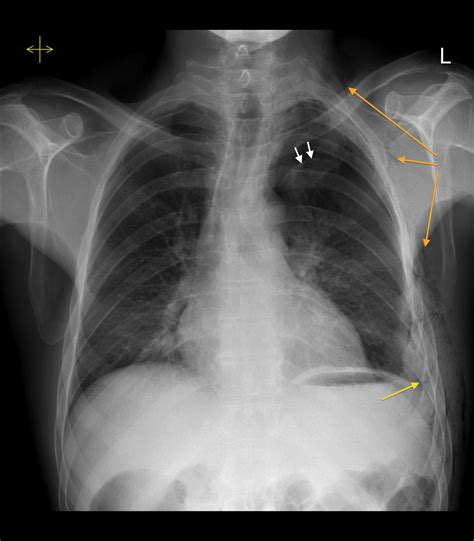

Interpreting an X Ray Of Pneumothorax requires a trained eye and a thorough understanding of chest anatomy. Radiologists look for specific signs that indicate the presence of pneumothorax, including:

• Absence of Lung Markings: In a normal X-ray, the lung tissue appears as a network of fine lines and markings. In pneumothorax, these markings are absent in the affected area, indicating the presence of air.

• Visceral Pleural Line: This is a thin, white line that represents the edge of the collapsed lung. It is often visible on the X-ray and helps to confirm the diagnosis of pneumothorax.

• Deep Sulcus Sign: This sign is seen on an upright chest X-ray and indicates a large pneumothorax. It appears as a deep, concave depression in the costophrenic angle, the area where the ribs meet the diaphragm.